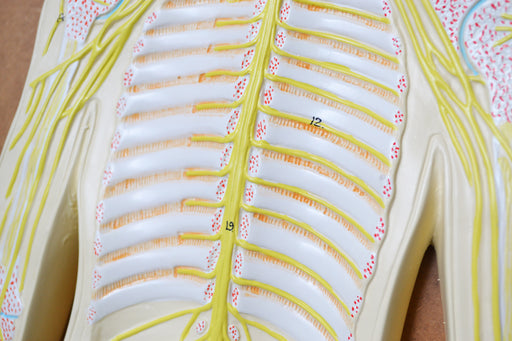

Nervous System Model, 32 Inch - Mounted - Includes Keycard - Great for Studying Structure - Eisco Labs

LIFELIKE DESIGN || 3-dimensional nervous system teaching demonstration model with lifelike design built from a custom mold DURABLE || Made of poly...

View full detailsAM16051 -